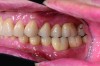

Fig 17. Left and right sagittal views of patient at 2-year follow-up. Interocclusal space was increased by crown lengthening and slight vertical openin

Figure 17

Fig 18. Left and right sagittal views of patient at 2-year follow-up. Interocclusal space was increased by crown lengthening and slight vertical openin

Figure 18